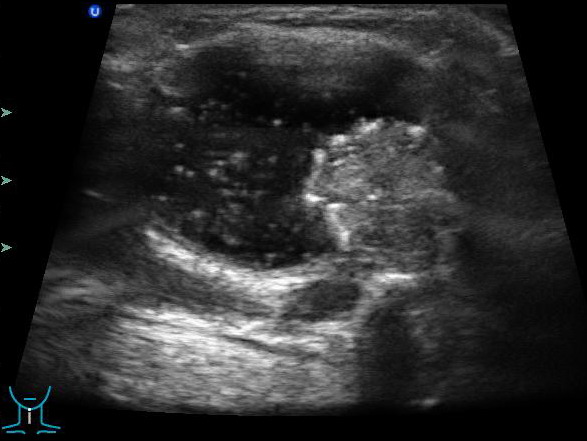

- Ультразвуковое исследование. Этот метод помогает различить срединные образования и кистозные лимфангиомы.